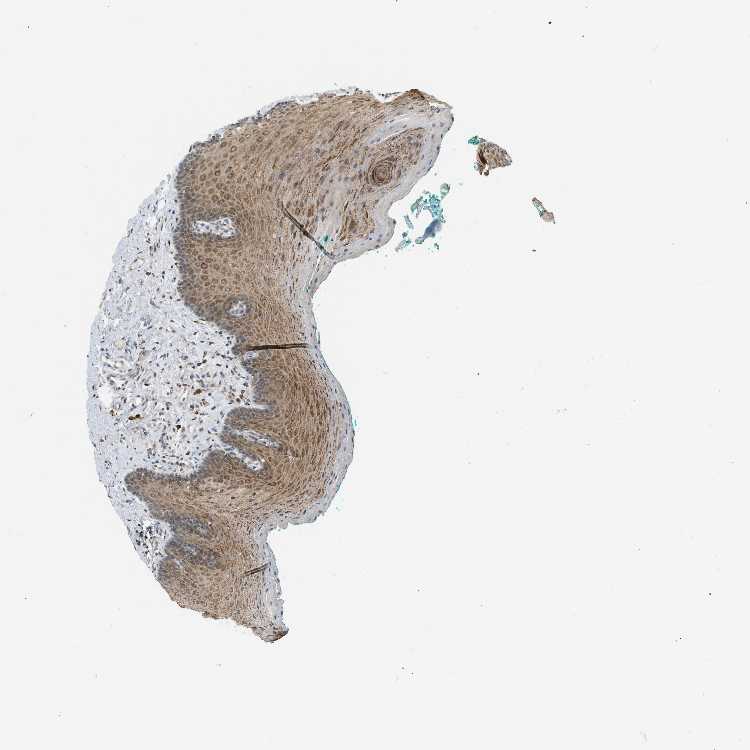

TISSUE PRIMARY DATA ORAL MUCOSA Show tissue menu

ORAL MUCOSA - Antibody stainingi

Antibody staining in the annotated cell types in the current human tissue is reported as not detected, low, medium, or high, based on conventional immunohistochemistry profiling in selected tissues. This score is based on the combination of the staining intensity and fraction of stained cells.

Each image is clickable and will lead to virtual microscopy that enables deeper exploration of all samples and also displays staining intensity scores, fraction scores and subcellular localization as well as patient and tissue information for each sample.

Antibody HPA015662Antibody HPA023277

Squamous epithelial cells MediumMedium